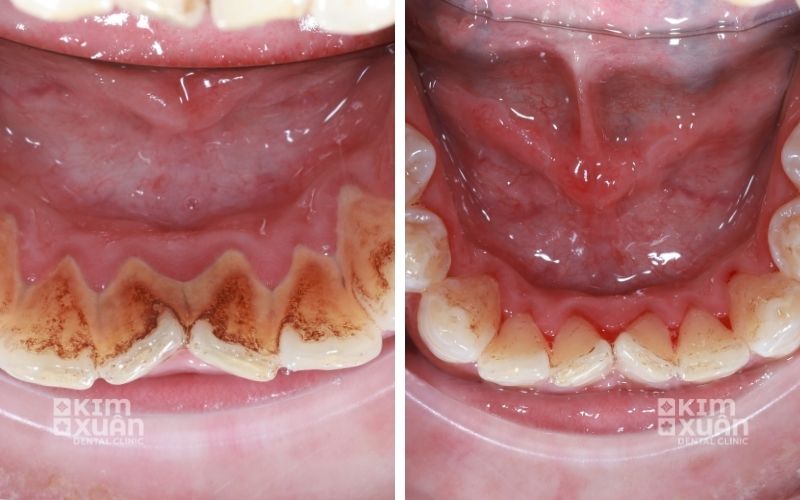

2.2. Cao răng tích tụ lâu ngày

Cao răng là môi trường thuận lợi cho vi khuẩn phát triển, khiến nướu sưng đỏ, chảy máu và viêm kéo dài, làm tăng nguy cơ viêm nha chu.

6.1. Cạo vôi răng - làm sạch chuyên sâu

Bác sĩ sẽ tiến hành lấy sạch mảng bám và cao răng bám quanh chân răng và dưới viền nướu. Đây là bước quan trọng giúp giảm viêm, hạn chế vi khuẩn và tạo điều kiện để nướu phục hồi khỏe mạnh.